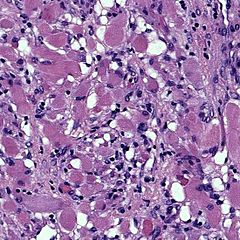

In the microscope we see large cells with a large cytoplasm full of glycogen vacuoles, between the vacuoles there are thin strips of cytoplasm between the nucleus and the cell membrane - the so-called spider cells. In addition, we detect actin and desmin in tumor cells, which proves that the tumor cells have a muscular origin. [1]